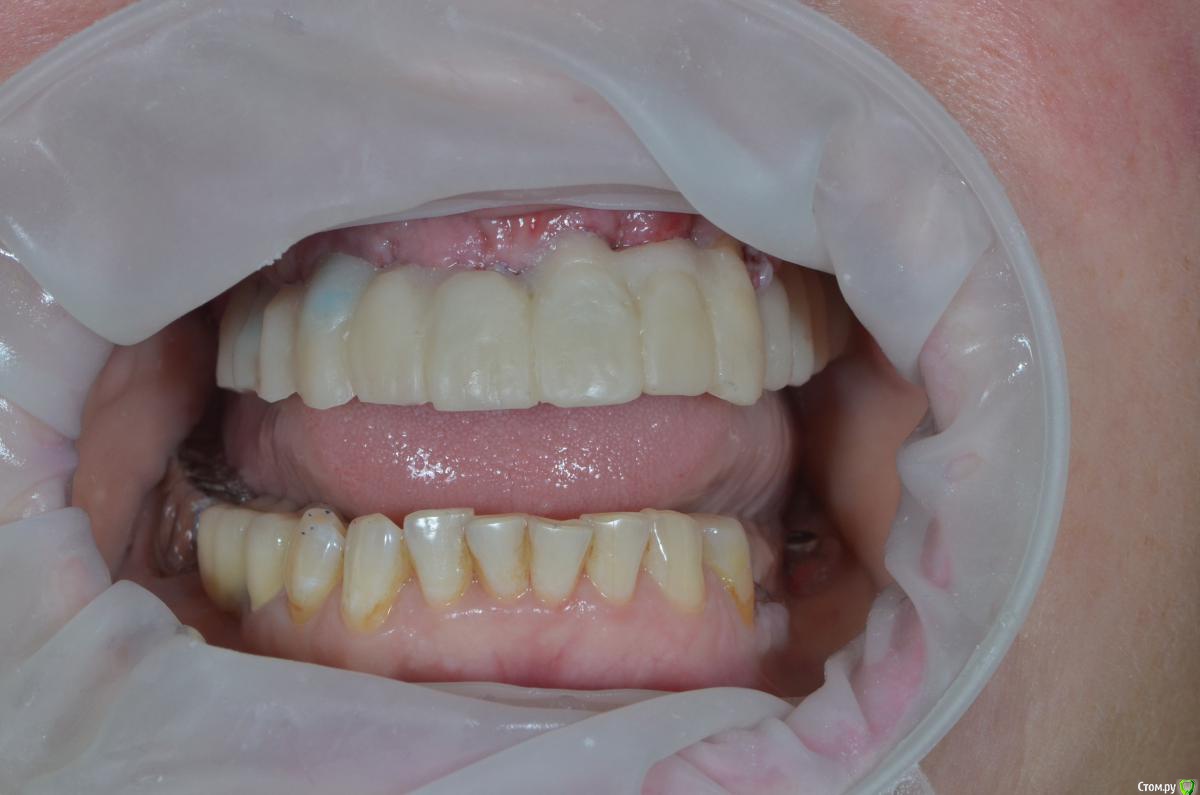

gangsta85 Опубликовано 22 декабря, 2018 Поделиться Опубликовано 22 декабря, 2018 Коллеги подскажите с тактикой протезирования?Есть проблема , хирург сильно укоротил зениты 21,22,23 .Работа с немедленной нагрузкой, торк 50н.Думаю сделать 2 фрезерованных моста с розовой десной, на зубы и имплантаты.благодарю) Ссылка на комментарий

gangsta85 Опубликовано 23 декабря, 2018 Автор Поделиться Опубликовано 23 декабря, 2018 На второй день появился вот такой отек, пока наблюдаем, если станет хуже думаю снять времянки, подкорректировать профиль. Ссылка на комментарий

vadyasti Опубликовано 2 января, 2019 Поделиться Опубликовано 2 января, 2019 (изменено) На второй день появился вот такой отек, пока наблюдаем, если станет хуже думаю снять времянки, подкорректировать профиль.Центральный сосочек зажат!Да и уздечку подрезать было бы не плохо. Изменено 2 января, 2019 пользователем vadyasti Ссылка на комментарий